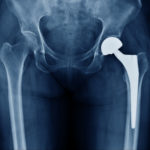

Joint Replacement Surgery and its Types

A joint is where two or more bones meet. Joint replacement surgery is a medical procedure that removes diseased and damaged tissue in joints and replaces them with artificial parts called prostheses. The prostheses are designed to replicate the movement of natural components of the joint. Joint replacement surgery is typically used to treat chronic, […]